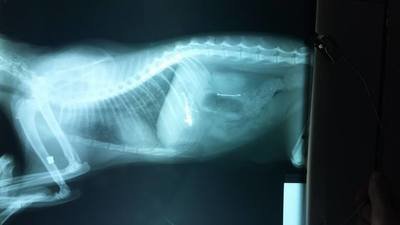

Se ve que a esta persona le molestan los animales, entonces procedió a tirarle o dejarle por ahi higado a los gatos, solo que entre y dentro de los bifes de higado les coloco de guarnicion alrededor de 15 a 20 anzuelos de todos los tamaños.

Gracias a el SiVET que nos atendieron de mil maravillas y pudieron retirarle los anzuelitos, lamentablemente uno se les escapo y lo termino de expulsar unos dias mas tarde con la caca.